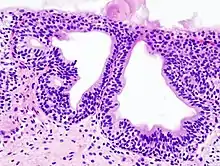

Cystitis glandularis is the transformation of mucosal cells lining the urinary bladder. They undergo glandular metaplasia, a process in which irritated tissues take on a different form, in this case that of a gland.[1] The main importance is in the findings of test results, in this case histopathology. They must distinguish a benign metaplastic change from the cancerous condition urothelial cell carcinoma.[2] It is a very common finding in bladder biopsies and cystectomies, and most often found in the trigone area. Cystitis glandularis lesions are usually present as small microscopic foci; however, occasionally it can form raised intramucosal or polypoid lesions. The cystitis glandularis lesions are within the submucosa.

There are two main types of cystitis glandularis, non-mucinous and mucinous (intestinal). The difference is in the cellular production of mucin, a normal feature of colonic and intestinal epithelial cells but not of urothelial cells. Another distinction is made between focal areas and diffuse involvement of the bladder. Whereas focal areas are more common, diffuse involvement is seen in chronically irritated bladders, such as in paraplegics or those with bladder stones or indwelling catheters. Individuals with diffuse intestinal-type cystitis glandularis are at increased risk for developing bladder cancer.

Cystitis glandularis arises from and merges with Von Brunn's nests, which are groups of urothelial cells (cells of urinary tract) within the lamina propria and submucosa, formed from budding from the surface mucosa. They are considered normal. Cystitis cystica is a similar lesion to cystitis glandularis, where the central area of the Von Brunn's nests have degenerated, leaving cystic lesions. Other metaplastic entities in the urinary bladder include squamous metaplasia and nephrogenic adenoma.